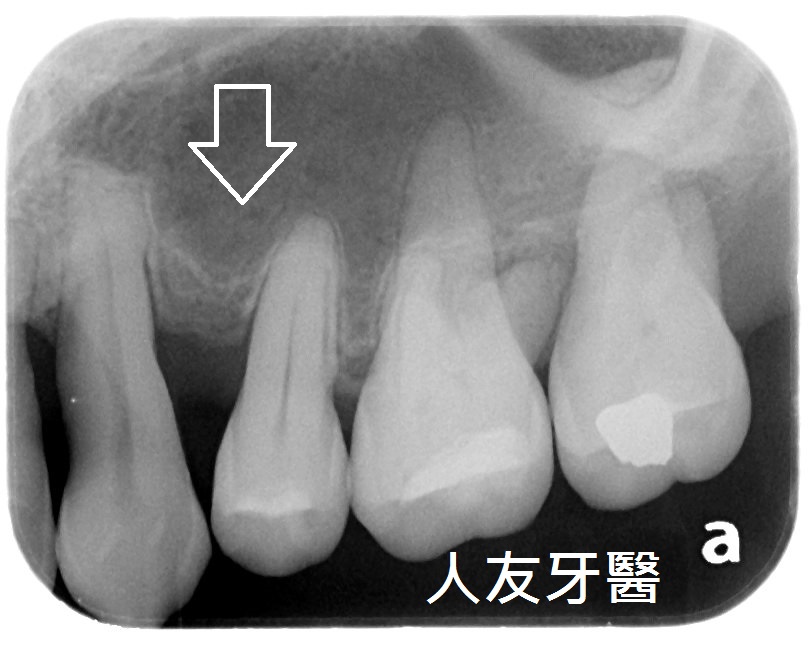

3.拔牙與骨釘:為騰出空間進行矯正,需要拔牙;骨釘用於輔助移動牙齒,初期可能會有異物感,但通常很快能適應。(下兩圖)

拔牙後放骨釘關閉空間原理與優點:

1.骨釘是植入在骨頭中的支撐點,提供穩定的錨定力量,確保牙齒移動的方向不受影響。

2.傳統矯正中移動牙齒可能造成其他牙齒跟著移動,使用骨釘可以精準控制牙齒的移動方向,讓拔牙後的縫隙能有效且正確地關閉。

3.骨釘可以大幅提升牙齒移動的效率,可能縮短矯正療程時間。

4.除了關閉拔牙空間,骨釘還能應用於骨性暴牙、嚴重深咬等情況,讓治療範圍更廣。